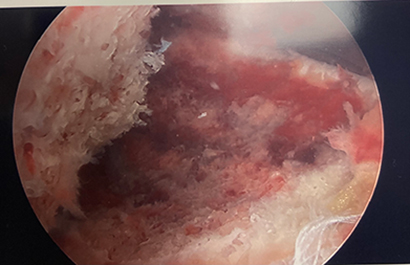

The fractures can be classified at Type 1 (minimally displaced), Type 2 (hinged with displacement of the anterior aspect), and Type 3 (completely displaced). Tibial spine fractures can be associated with other injuries including meniscal tears, bone bruising, cartilage injuries, and other non-ACL ligamentous injuries. Plain radiographs can be used to diagnose this injury, but MRI may be needed to identify concomitant injuries to the soft tissue structures. Treatment includes nonoperative management for Type 1 and some Type 2 injuries (reduction within a few millimeters of anatomic to be acceptable). Surgical fixation is indicated for irreducible Type 2 and Type 3 injuries. Surgery is usually performed arthroscopically. Fixation can be accomplished with sutures, suture anchors, or screws. Approach and fixation are often chosen based on fracture characteristics. Figure 3 shows an arthroscopic image of an avulsed tibial spine fracture. Figure 4 shows the ACL tensioned once the tibial spine is reduced while Figure 5 shows the tibial spine fragment reduced and fixed with bioabsorbable screws.

Figure 3